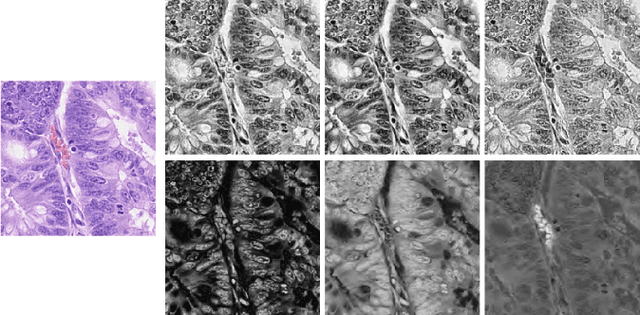

Abstract:Nuclei segmentation and classification is the first and most crucial step that is utilized for many different microscopy medical analysis applications. However, it suffers from many issues such as the segmentation of small objects, imbalance, and fine-grained differences between types of nuclei. In this paper, multiple different contributions were done tackling these problems present. Firstly, the recently released "ConvNeXt" was used as the encoder for HoVer-Net model since it leverages the key components of transformers that make them perform well. Secondly, to enhance the visual differences between nuclei, a multi-channel color space-based approach is used to aid the model in extracting distinguishing features. Thirdly, Unified Focal loss (UFL) was used to tackle the background-foreground imbalance. Finally, Sharpness-Aware Minimization (SAM) was used to ensure generalizability of the model. Overall, we were able to outperform the current state-of-the-art (SOTA), HoVer-Net, on the preliminary test set of the CoNiC Challenge 2022 by 12.489% mPQ+.